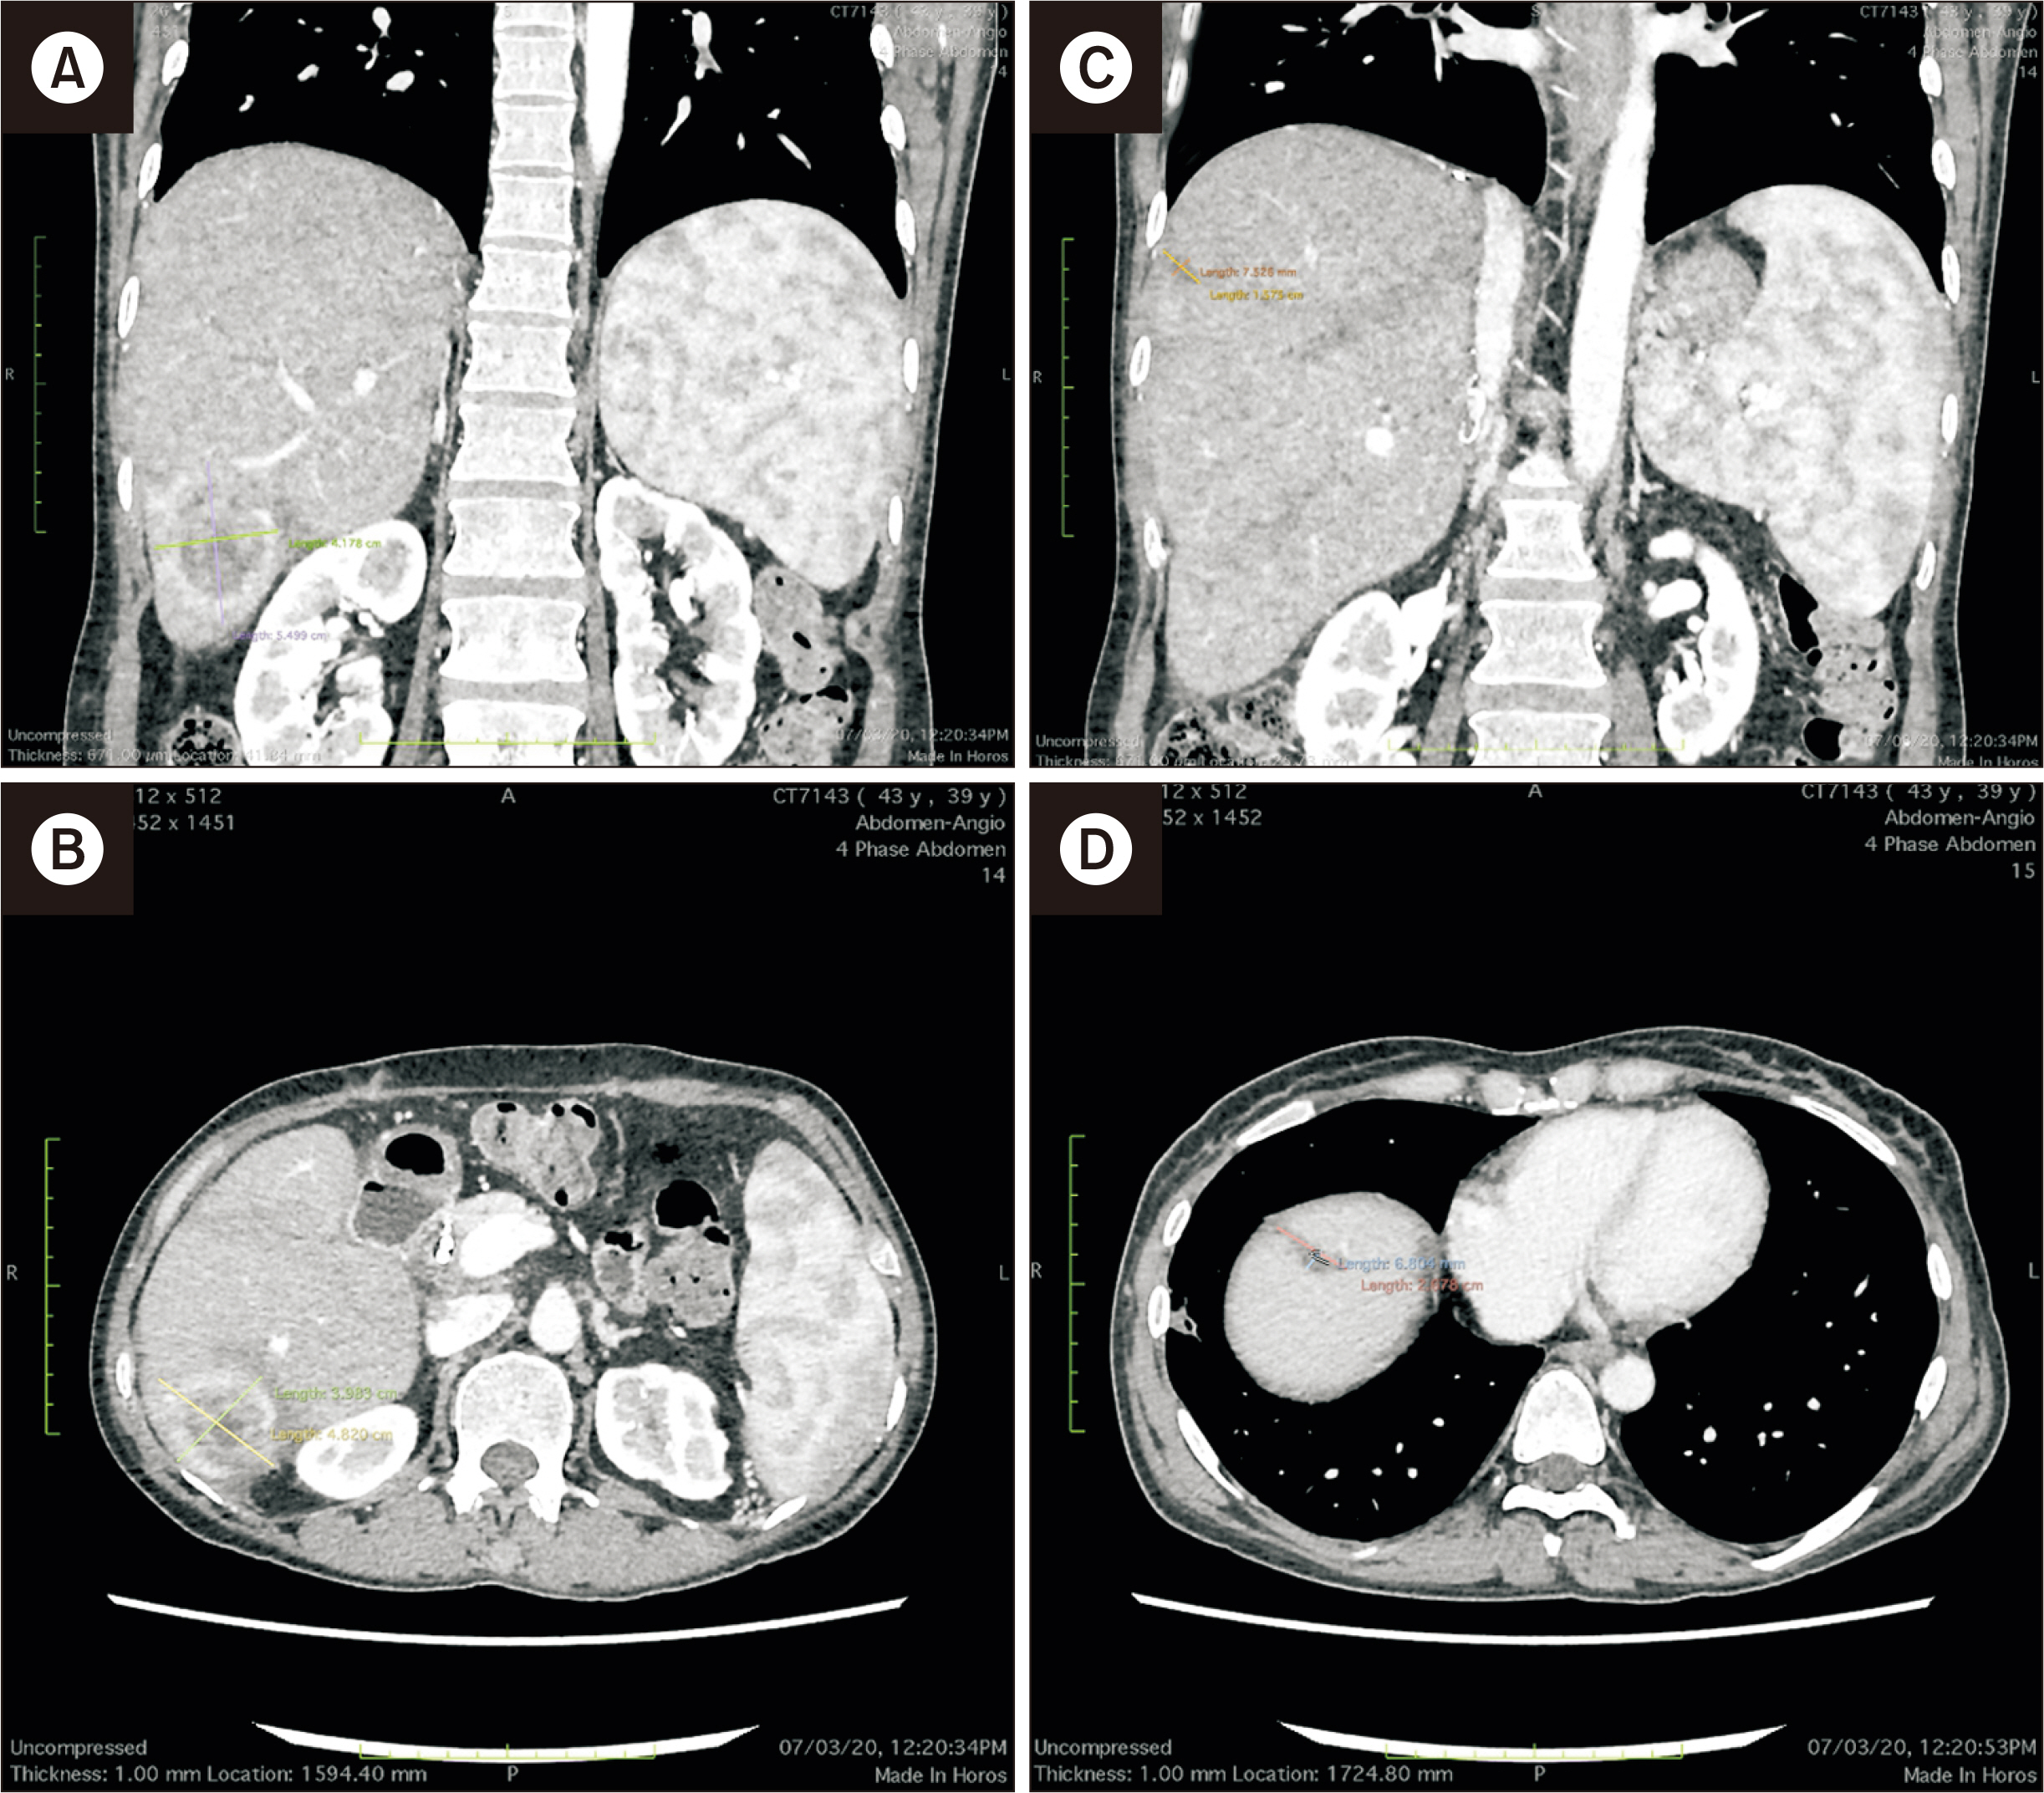

- Kaposi sarcoma following solid organ transplantation is a rare and underreported complication, with few cases documented globally concerning its origin from liver grafts. This case report describes an Asian woman who developed Kaposi sarcoma in a liver graft following living donor liver transplantation for end-stage liver disease resulting from hepatitis D virus. In accordance with current guidelines, standard immunosuppression was discontinued, and mammalian target of rapamycin (mTOR) inhibitors were initiated. The use of mTOR inhibitors led to the complete resolution of the liver graft lesions within 9 months. However, subsequent follow-up revealed several complications, including late anastomotic biliary stricture, extensively drug-resistant Klebsiella pneumoniae infection, and subtotal hydrothorax. These complications required intensive care unit admission, biliary stenting, oxygen therapy, and pleural drainage. Despite the severity of her condition, the patient fully recovered and showed no signs of recurrence throughout the 64-month follow-up period. To our knowledge, this is the first reported case of Kaposi sarcoma in a liver graft with such an extended follow-up.

Figure

Article10. Gupta S, Ghuman SS, Buxi TB, Sudarsan H, Sethi S, Yadav AK, et al. 2015; Imaging of Kaposi sarcoma in a transplanted liver: a rare case report. Egypt J Radiol Nucl Med. 46:335–8. DOI: 10.1016/j.ejrnm.2015.02.007.